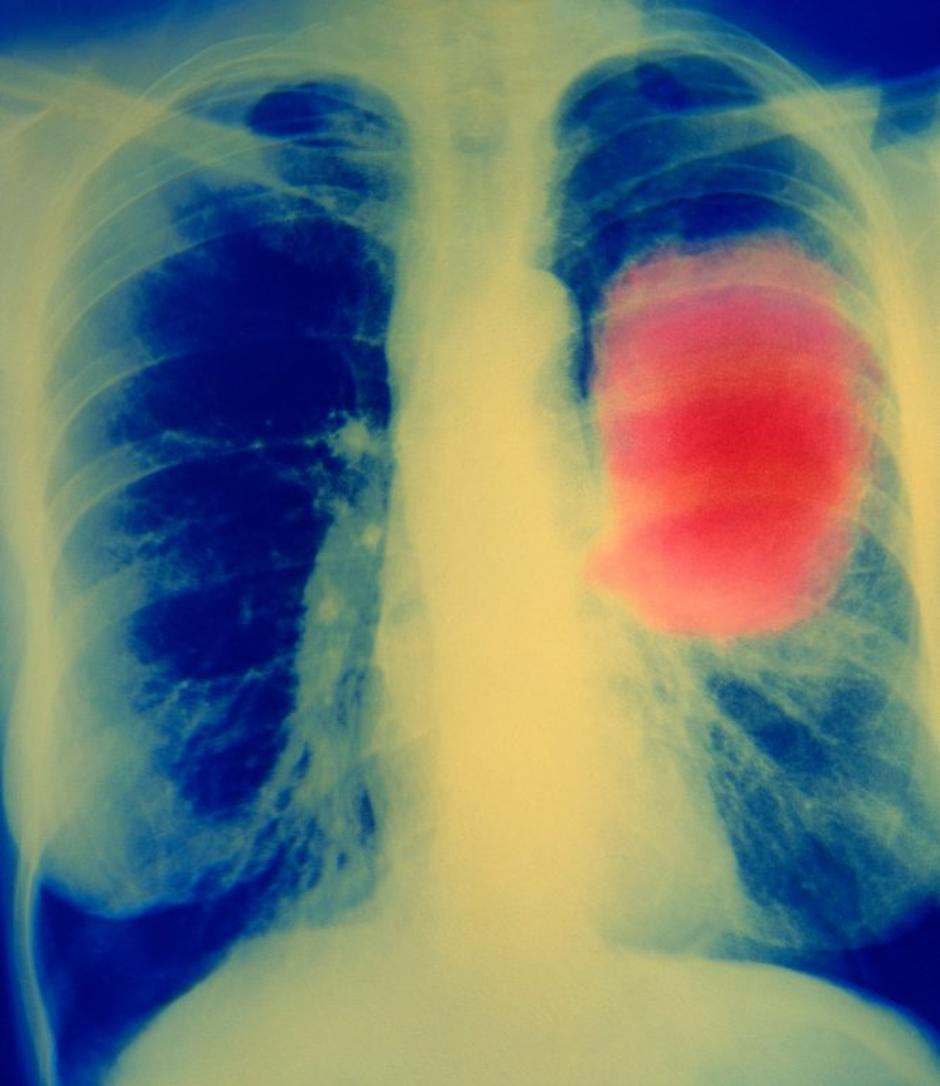

Rak na pljučih | Avtor: Profimedias Profimedias

Tveganje največje pri raku grla ter pljučnem raku